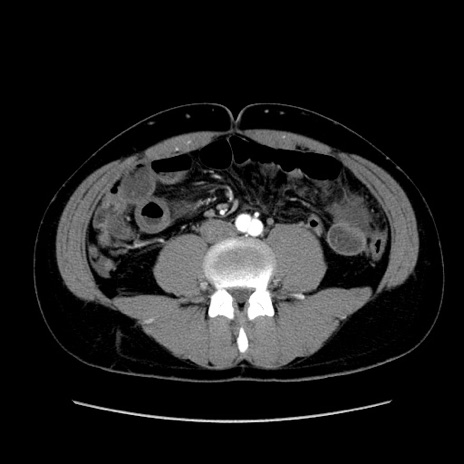

症例36(横断像)

【症例】20歳代 男性

【主訴】心窩部痛

【現病歴】今朝より上腹部痛あり。一旦軽快していたが再度出現したため救急要請。昨日夕に白身の魚を含む刺身を食べた。

【身体所見】BP 136/89mmHg、HR 74/min、BT 37.0℃、腹部:膨満、軟、心窩部に圧痛あり。反跳痛なし、筋性防御なし、腸雑音やや亢進あり。

【データ】WBC 17700、CRP 0.48